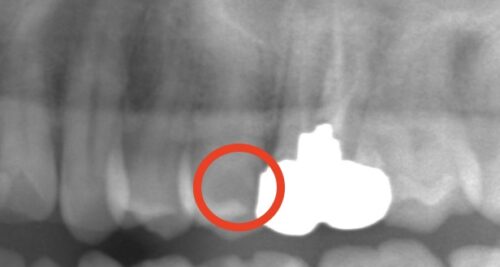

審美治療 症例集 虫歯治療

銀歯を白くしたい…セラミックインレーで自然にきれいにできるって知っていますか?

「できるだけ白いものに変えたい」そんなご相談から始まった症例です

「銀歯が目立つからきれいにしたい…… 歯科コラム